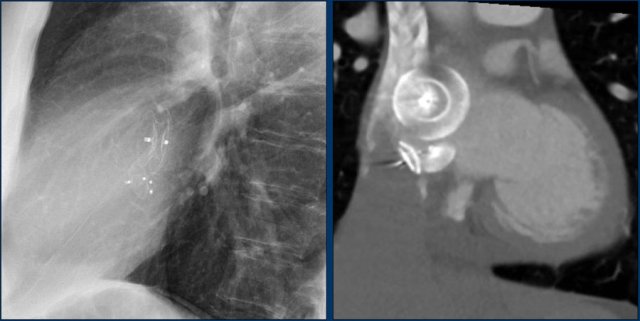

Here an example of an ICD with wires in the right atrial appendage, the apex of the right ventricle and a lead to the left ventricle in the posterior coronary vein.

You can recognize the two shock coils of the ICD as thicker white bands along the course of the lead.

This patient has three leads:

1. Right atrial lead

2. Right ventricular lead (with shock coil)

3. Left ventricular lead in coronary sinus and cardiac vein